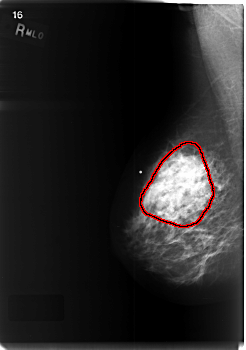

ics_version 1.0 filename C-0471-1 DATE_OF_STUDY 8 9 1997 PATIENT_AGE 48 FILM FILM_TYPE REGULAR DENSITY 2 DATE_DIGITIZED 28 12 1998 DIGITIZER LUMISYS LASER SEQUENCE LEFT_CC LINES 5696 PIXELS_PER_LINE 3520 BITS_PER_PIXEL 12 RESOLUTION 50 NON_OVERLAY LEFT_MLO LINES 5416 PIXELS_PER_LINE 4112 BITS_PER_PIXEL 12 RESOLUTION 50 NON_OVERLAY RIGHT_CC LINES 5768 PIXELS_PER_LINE 4056 BITS_PER_PIXEL 12 RESOLUTION 50 OVERLAY RIGHT_MLO LINES 5936 PIXELS_PER_LINE 4168 BITS_PER_PIXEL 12 RESOLUTION 50 OVERLAY |

FILE: C_0471_1.RIGHT_MLO.OVERLAY TOTAL_ABNORMALITIES 1 ABNORMALITY 1 LESION_TYPE MASS SHAPE ASYMMETRIC_BREAST_TISSUE MARGINS ILL_DEFINED ASSESSMENT 5 SUBTLETY 5 PATHOLOGY MALIGNANT TOTAL_OUTLINES 1 BOUNDARY |